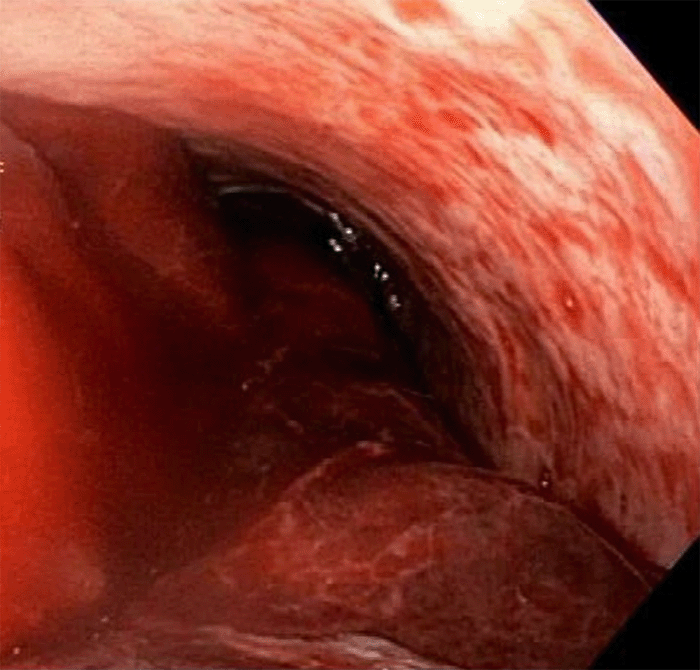

The patient subsequently underwent uneventful angioembolization of the left gastric artery and T9 right intercostal artery. However, the patient continued to have ongoing hemorrhage with transfusion requirements, including 17u PRBC, 6u FFP, 2u PLT, and 2u cryoprecipitate. After aggressive saline lavage, repeat upper endoscopy identified focal distal esophageal arterial bleeding. Hemostasis was unsuccessful despite an injection of 2 cc 1:10000 epinephrine solution and attempted mucosal banding (Figure 2).

Figure 2. Repeat Upper Endoscopy Demonstrated Distal Esophagitis, Adherent Clot to Anterolateral Distal Esophagus, and Active Arterial Bleeding (not shown). Published with Permission